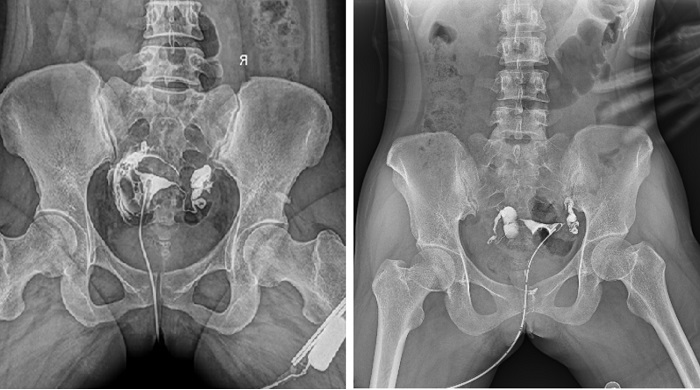

輸卵管造影檢查可根據(jù)造影劑在輸卵管及盆腔內(nèi)的顯影情況了解輸卵管是否通暢、阻塞部位及宮腔形態(tài),是超聲、CT、核磁、宮腔鏡、腹腔鏡、輸卵管鏡等所無法替代的。作為目前普放領域最先進的影像設備,多功能動態(tài)DR進行子宮輸卵管造影檢查,大大超越了過去的檢查技術,更加精準、便捷、高效。

相較于傳統(tǒng)胃腸機,動態(tài)DR矩形采集面積大,一次曝光即可顯示整個盆腔,大幅減少觀察時間,可控的瞬時照射避免受檢者吸收過多的X線,對育齡期女性的檢查尤為重要。毫秒級時間內(nèi)高清點片,可以在造影劑流動的過程中完成拍片,抓拍到關鍵圖像,更加清楚地了解到管腔的具體通暢情況及堵塞部位,對檢查及診斷有非常重要的價值。

子宮輸卵管造影

此外,應用動態(tài) DR 進行子宮輸卵管造影,還可以在加壓推注下,使部分輸卵管輕、中度堵塞的患者得以通暢,起到一定的治療作用。